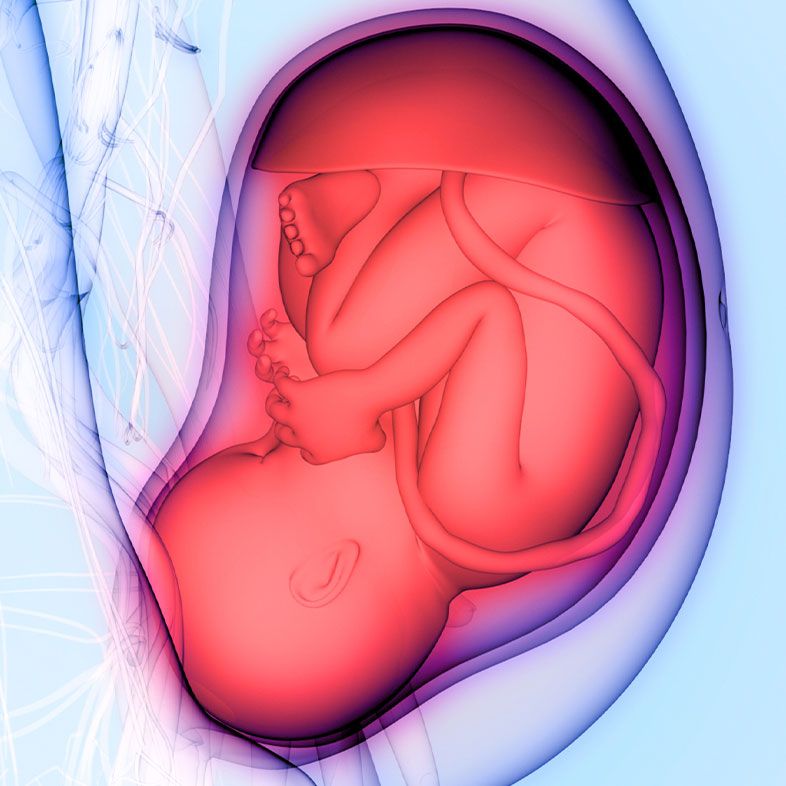

Normal pre-delivery baby cephalic position. Sometimes it is impossible to diagnose abnormal fetal positions without using ultrasound.